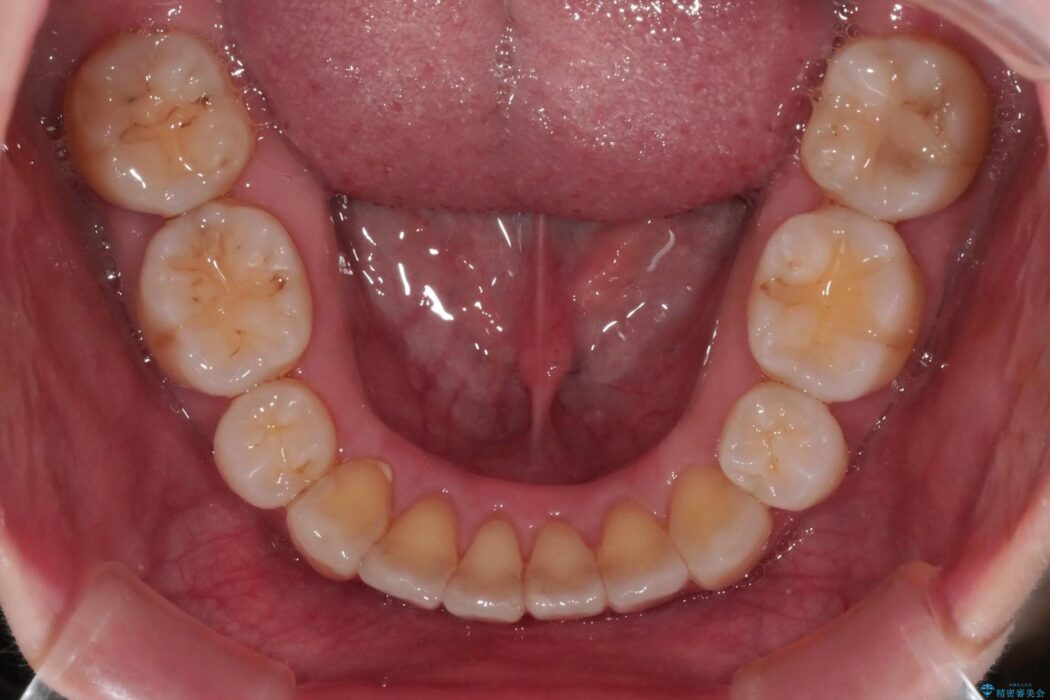

抜歯矯正後の上の前歯の後戻りが気になるとご来院された患者様です。

歯と歯の間を削るのと、歯列のU字型のアーチを僅かに外側に広げる事でスペースを作り、前歯の角度の改善をしました。

保定装置は、マウスピースと前歯の裏側を細いワイヤーで固定(ボンディングリテーナー)を併用していただいてます。